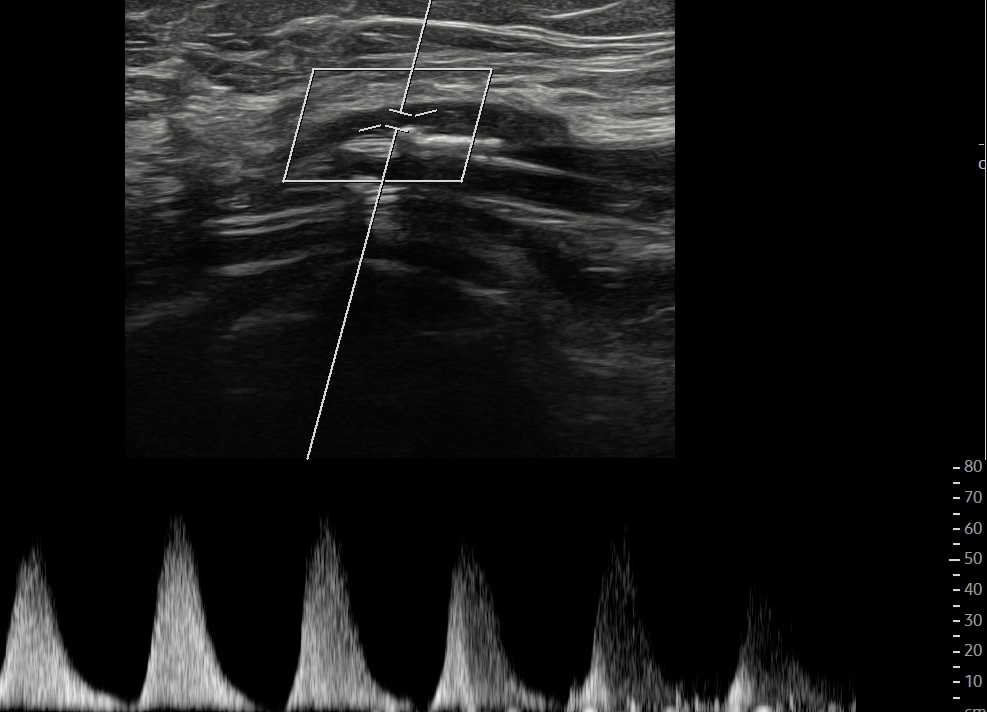

Dado el acceso a ecografía clínica en el centro de salud, se realiza la misma.

Hallazgos ecográficos

Se identifican placas de ateroma en ambas arterias femorales comunes, con pérdida del flujo diastólico, hallazgo sugestivo de enfermedad aterosclerótica significativa.

Los engrosamientos parietales difusos o focales sugieren aterosclerosis. En territorios de alta resistencia, el flujo normal es trifásico: un pico sistólico anterógrado, una corta fase reversa por resistencia periférica y un componente diastólico anterógrado de baja velocidad. El flujo arterial sano es laminar, con velocidades habitualmente menores de 1,5 m/s. Las estenosis hemodinámicamente significativas reducen más del 50% de la luz vascular y producen aliasing en Doppler color, con velocidades superiores a 1,3 m/s. Distalmente a una estenosis grave, los flujos se vuelven monofásicos, variando su resistencia según la vasodilatación distal.